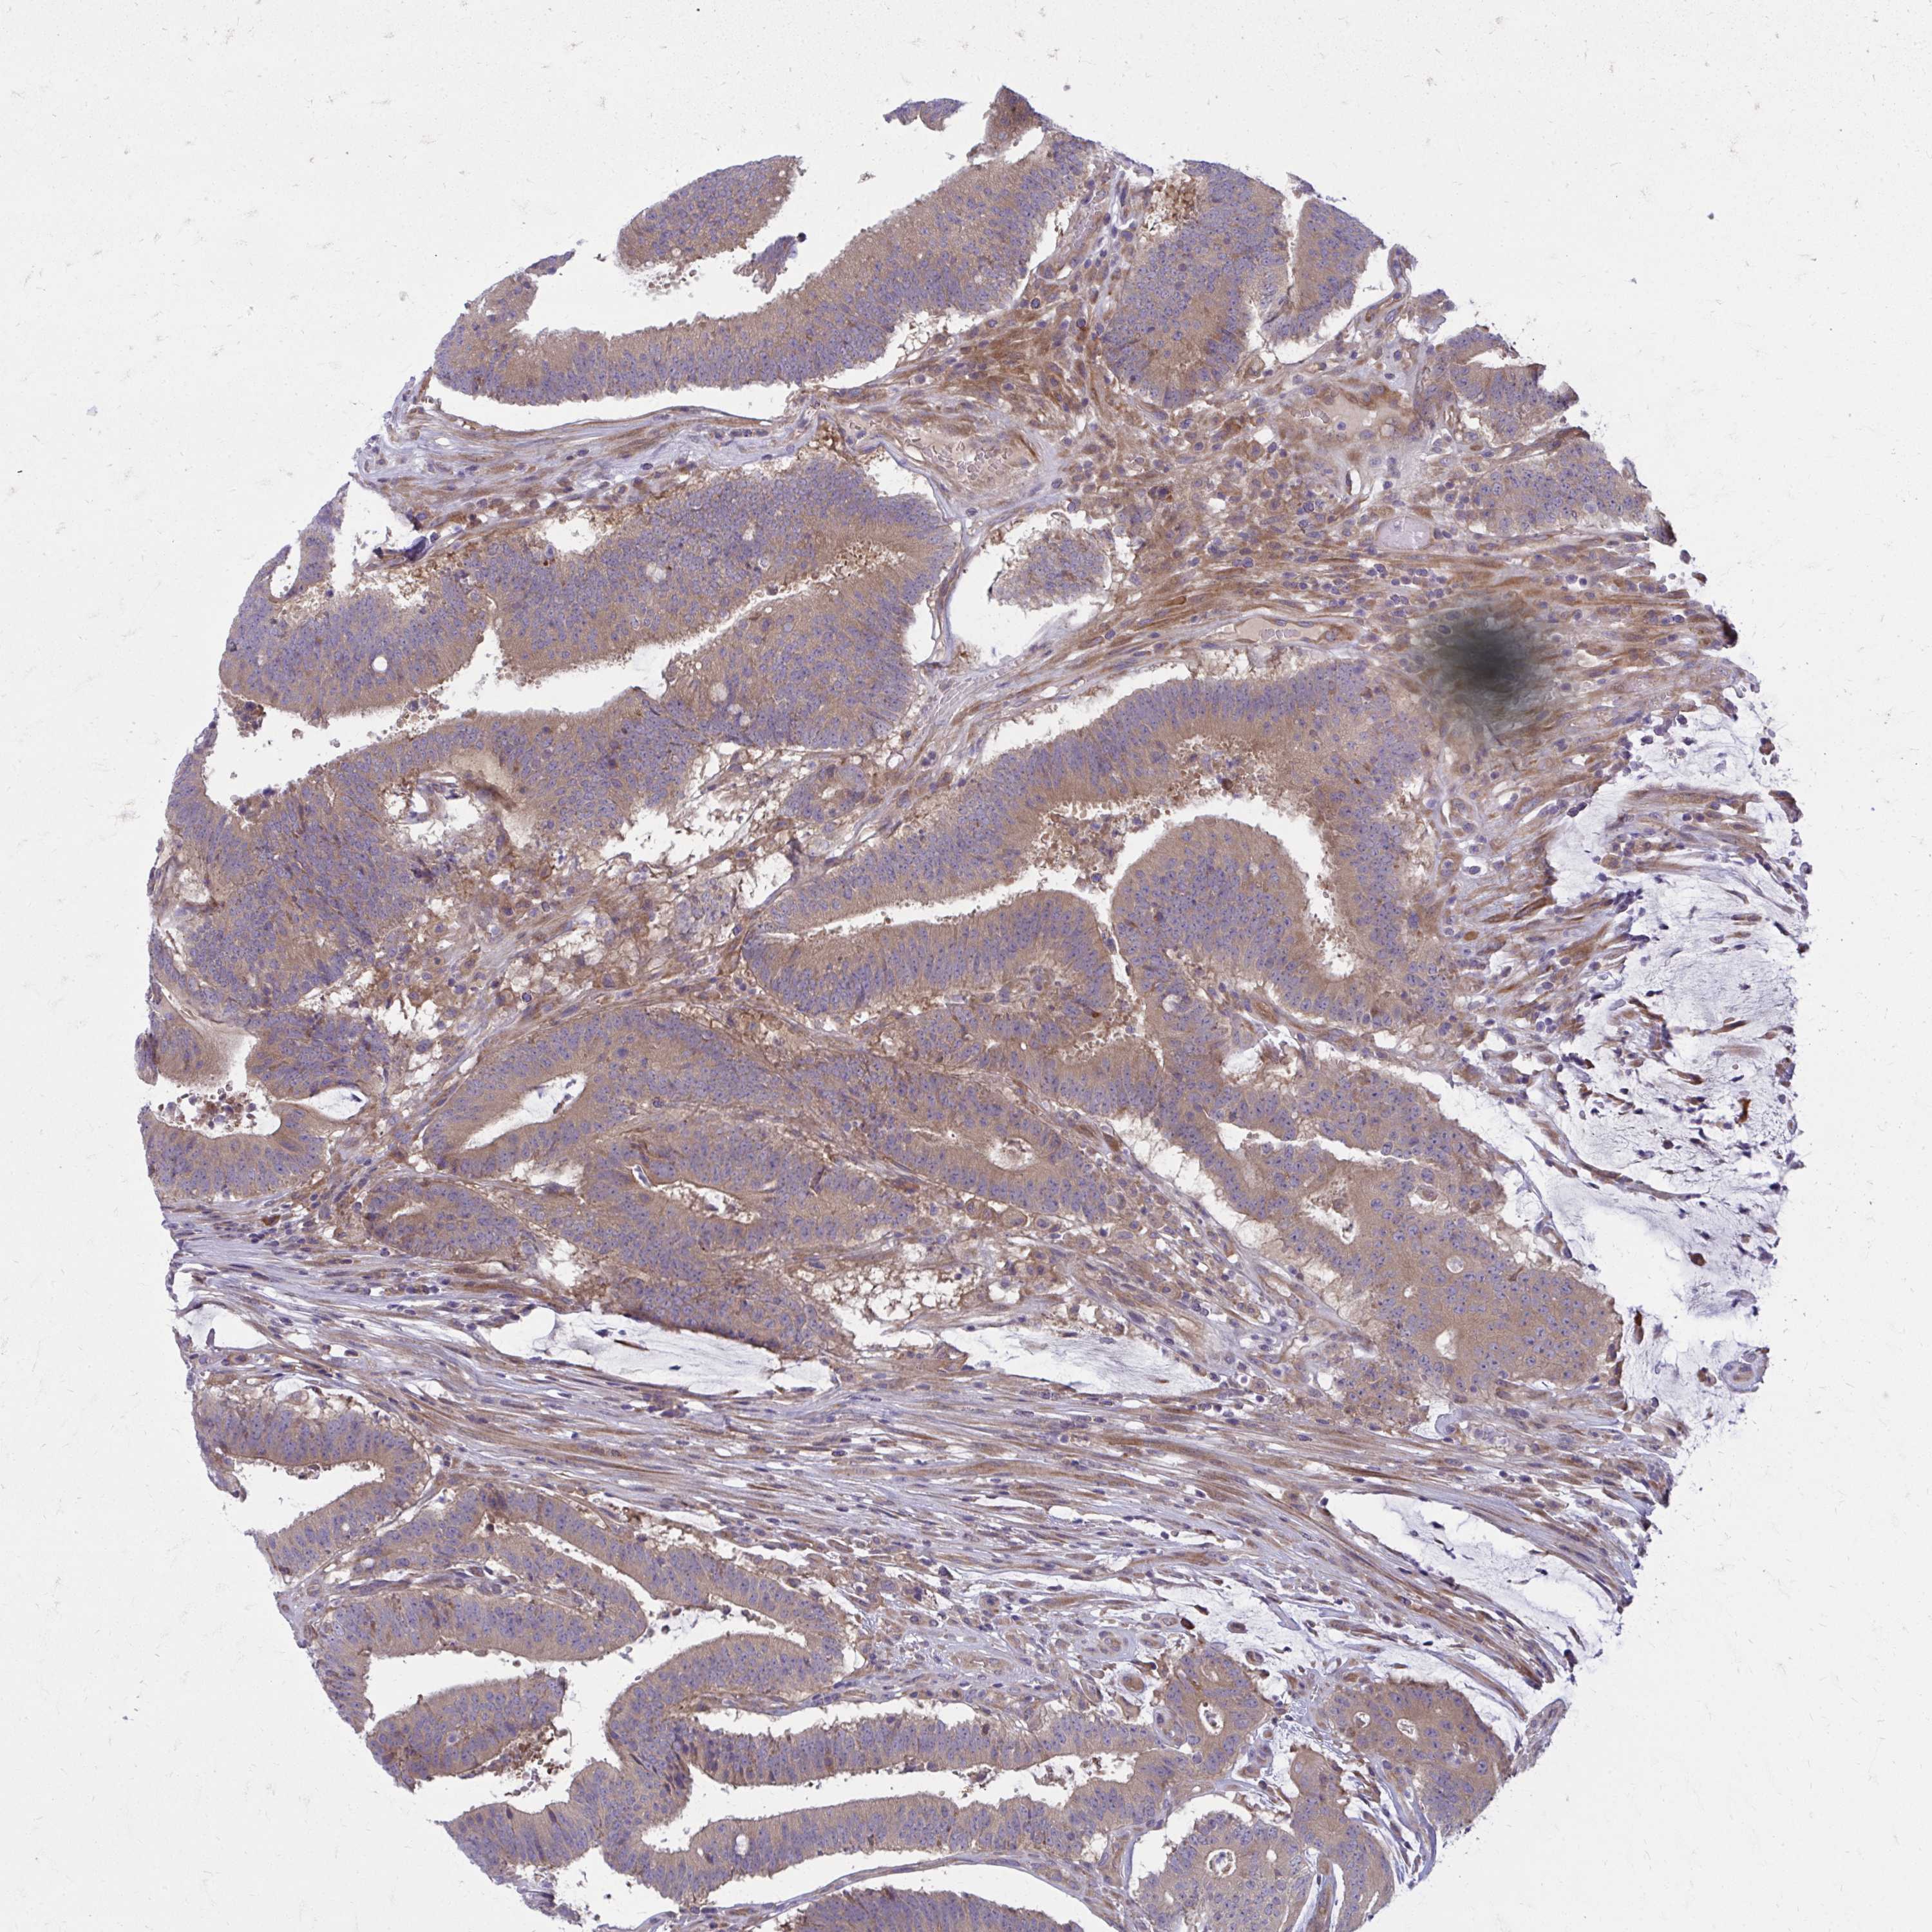

CANCER COLORECTAL CANCER Show tissue menu

Colorectal cancer

Human cancer

Colon adenocarcinoma

Rectum adenocarcinoma